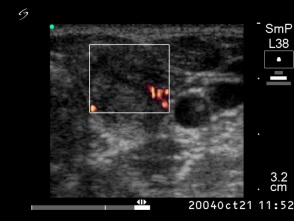

Six months after the therapy (second row of images):

Clinical presentation: the complaints of the patient have disappeared and she did not feel the lesion in the left lobe.

Palpation: the lesion in the left lobe became non-palpable.

Ultrasonography the volume of the treated nodule decreased to less than one-quarter of the original size.

Functional state: euthyroidism with TSH 1.56 mIU/L.